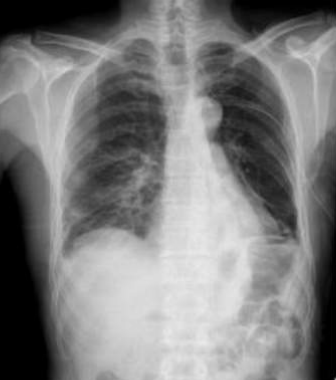

âȘ Table 5: We visualize samples of the generated reports for three cases. We bold the identical descriptions, underline the additional identified findings, and in red the failure findings..

X-ray Image | Baseline | M2TR | R2Gen | Ours |

![]() |

Pneumothorax gauche de grande abondance./OpacitĂ© rĂ©ticulo-micronodulaire avec verre dĂ©poli de lâhĂ©michamp pulmonaire gauche avec individualisation dâune volumineuse bulle apical gauche./ | Pneumothorax droit de grande abondance./ OpacitĂ© rĂ©ticulo-micronodulaire dans lâhĂ©michamp pulmonaire droit, avec verre dĂ©poli et prĂ©sence d'une bulle apicale droite importante./ | Pneumothorax gauche modĂ©rĂ©./ OpacitĂ©s rĂ©ticulo-micronodulaires avec zones de verre dĂ©poli Ă©tendues sur lâhĂ©michamp pulmonaire droit./ | Pneumothorax bilatĂ©ral de grande abondance./ PrĂ©sence d'opacitĂ© rĂ©ticulo-micronodulaire avec aspect de verre dĂ©poli sur les deux hĂ©michamps pulmonaires, plus de grande bulle apicale sur le cĂŽtĂ© gauche./ SurĂ©levation de la coupole diaphragmatique droite avec trachĂ©e tirĂ©e vers la droite./ |